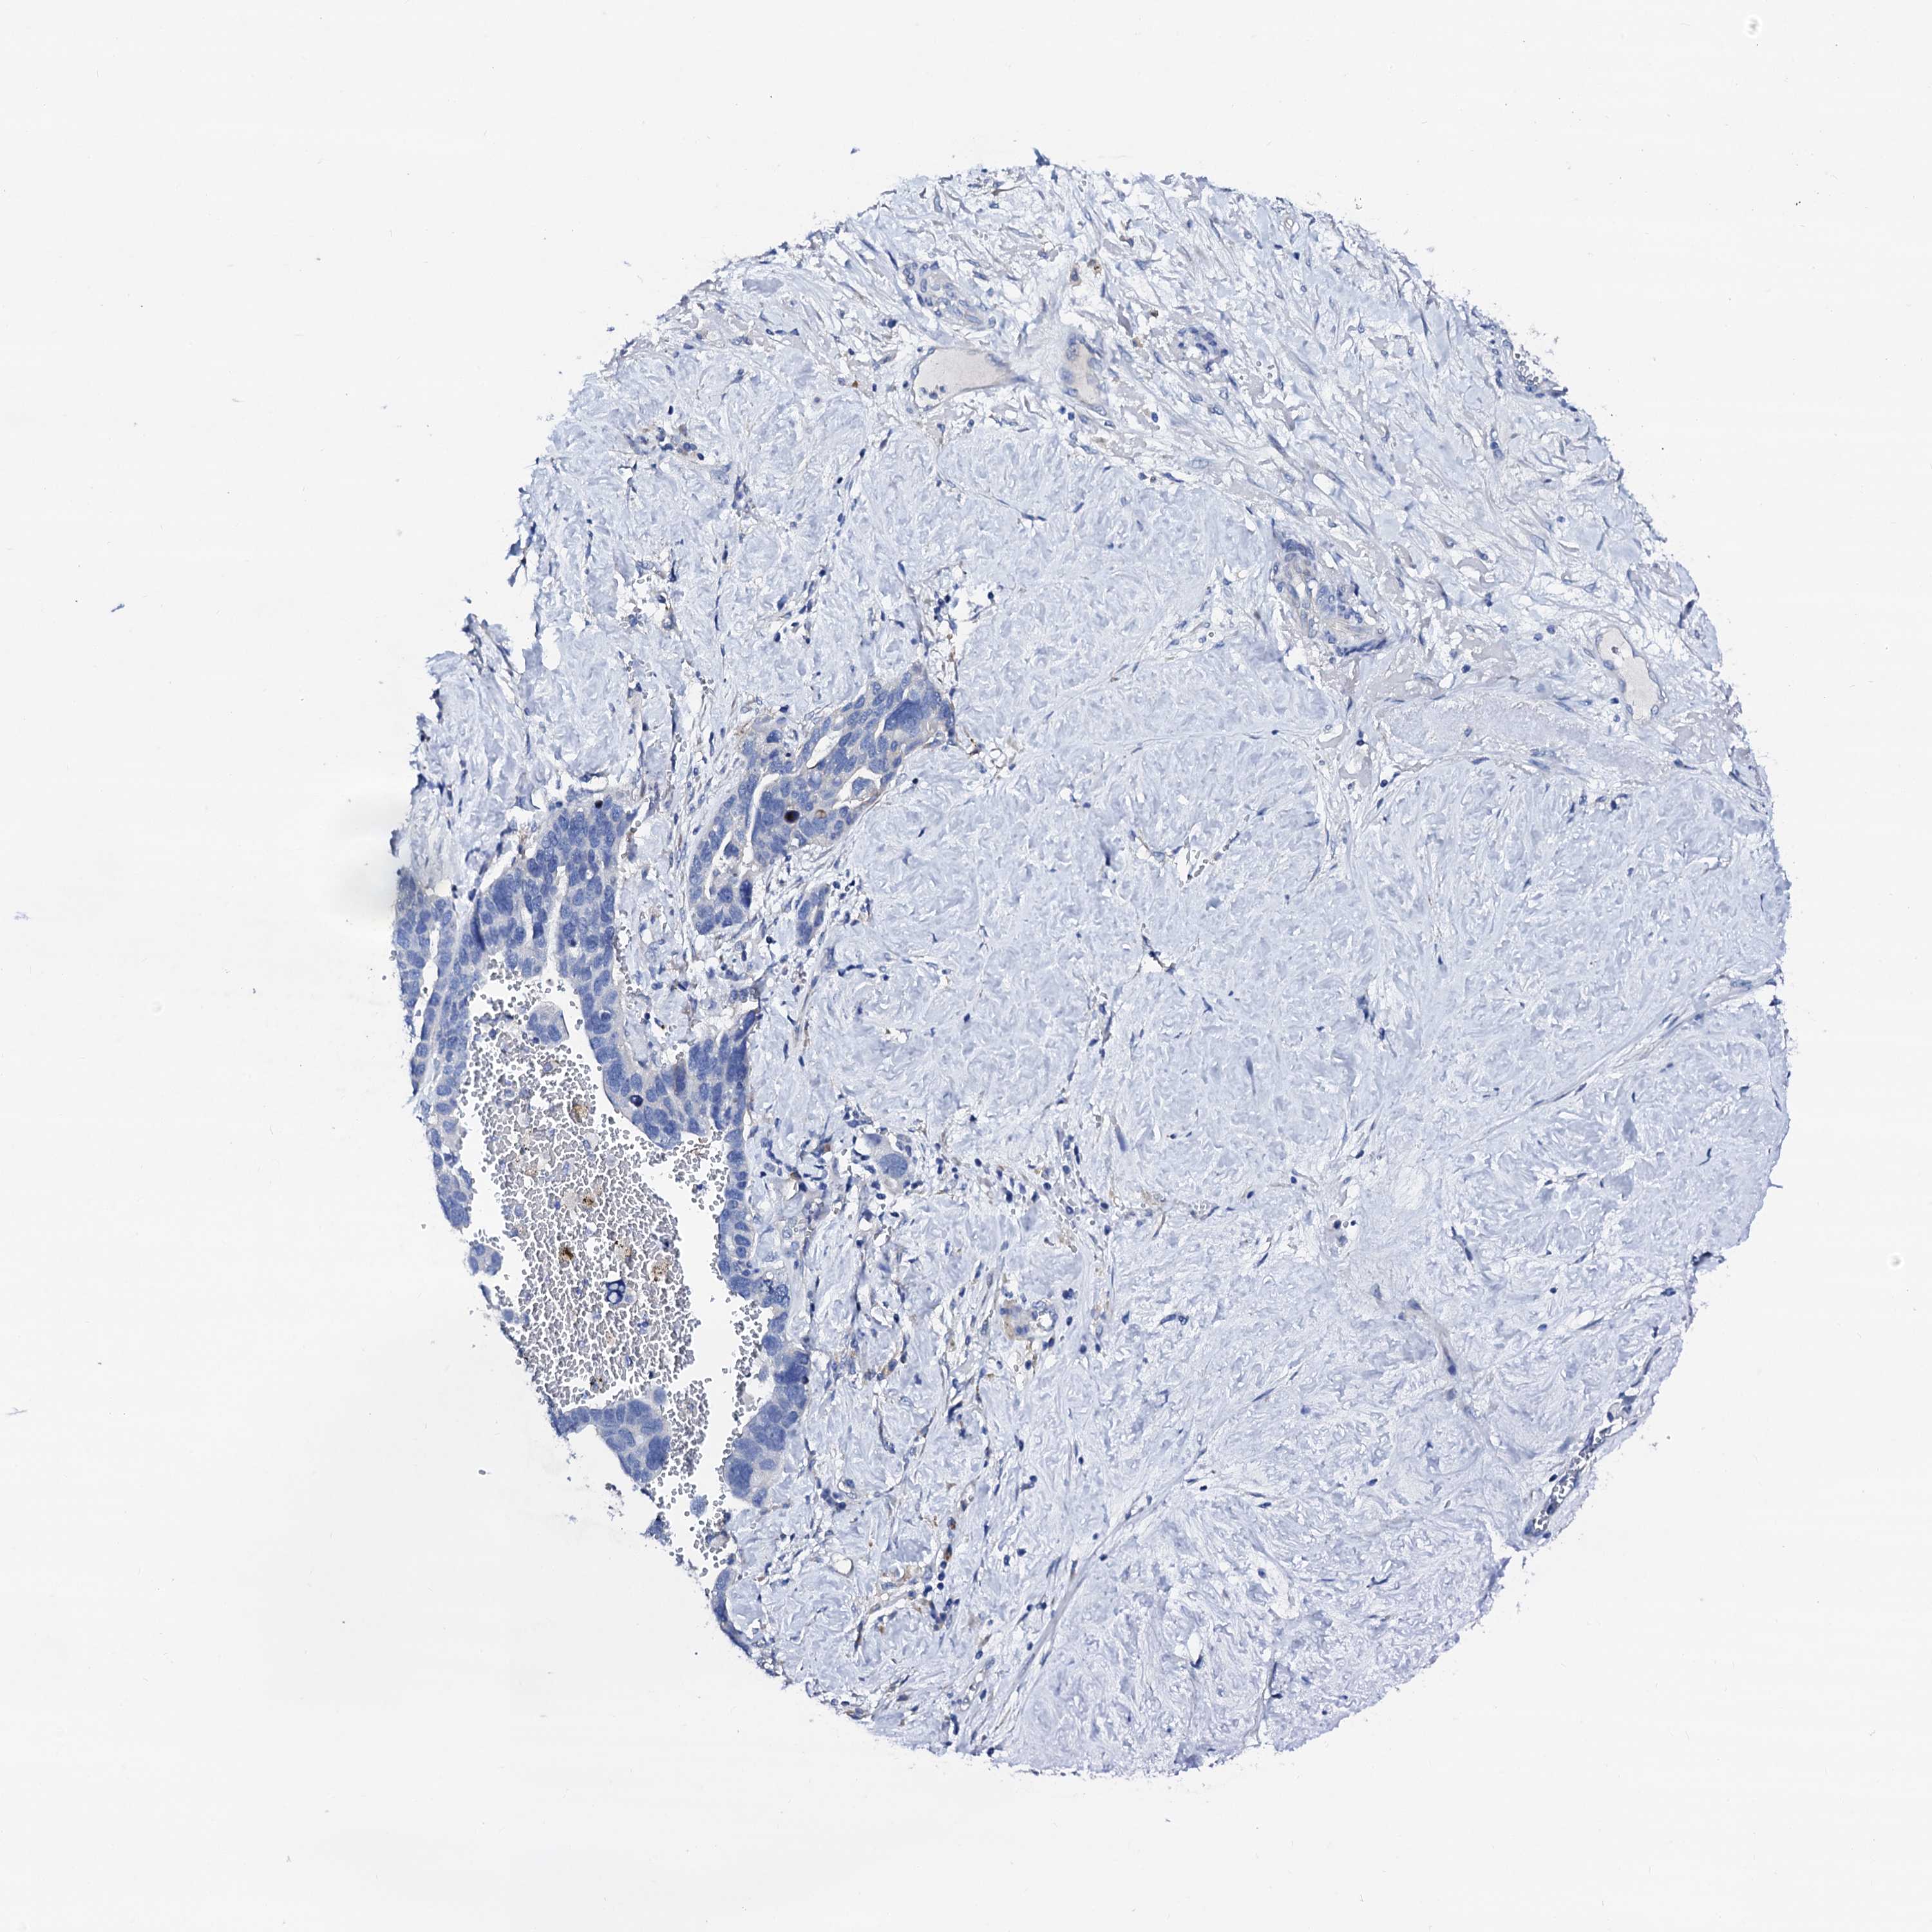

OVARIAN CANCER - Protein expressioni

A mouse-over function shows sample information and annotation data. Click on an image to view it in a full screen mode. Samples can be filtered based on level of antibody staining by selecting one or several of the following categories: high, medium, low and not detected. The assay and annotation is described here.

Note that samples used for immunohistochemistry by the Human Protein Atlas do not correspond to samples in the TCGA dataset.

Antibody stainingi

Antibody staining in the annotated cell types in the current human tissue is reported as not detected, low, medium, or high, based on conventional immunohistochemistry profiling in selected tissues. This score is based on the combination of the staining intensity and fraction of stained cells.

Each image is clickable and will lead to virtual microscopy that enables deeper exploration of all samples and also displays staining intensity scores, fraction scores and subcellular localization as well as patient and tissue information for each sample.

Antibody HPA038226

Antibody HPA058226

Cystadenocarcinoma, serous, NOS

Carcinoma, endometroid

Cystadenocarcinoma, mucinous, NOS

Carcinoma, NOS